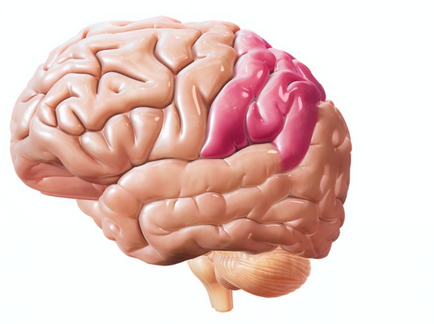

Lobilor frontali sunt responsabili pentru acțiunile arbitrare. organizarea și planificarea, precum și dezvoltarea de competențe. Este datorită lor treptat locul de muncă, care inițial părea dificil și evaziv, devine automat și nu necesită mult efort. În cazul în care lobilor frontali sunt deteriorate, o persoană este condamnată să facă de fiecare dată când munca lor, ca și cum, pentru prima dată, de exemplu, pauze de capacitatea sa de a găti, mergeți la cumpărături, etc. O altă variantă a tulburărilor asociate cu lobilor frontali - „fixarea“ pe acțiunile efectuate de către pacient, sau perseverenta. Perseverație poate manifesta ca în vorbire (repetarea acelorași cuvinte sau fraze întregi), precum și în alte activități (de exemplu, obiecte de schimbare a vitezelor fără țintă din loc în loc).

Cele dominante (de obicei, stânga) lobului frontal multe domenii responsabile pentru diferite aspecte ale vorbirii umane, atenția și gândirea abstractă.

Notă, în cele din urmă, o parte a lobilor frontali în menținerea poziției verticale a corpului. În cazul în care învinge pacientul are un mers mărunțire fină și o incovoierea spatelui.

Față și lobul temporal medial asociată cu simțul mirosului. Astăzi a demonstrat că apariția sentiment de probleme de miros de vârstă a unui pacient poate fi un semn al unui curs de dezvoltare, dar nu a fost încă diagnosticat boala Alzheimer.